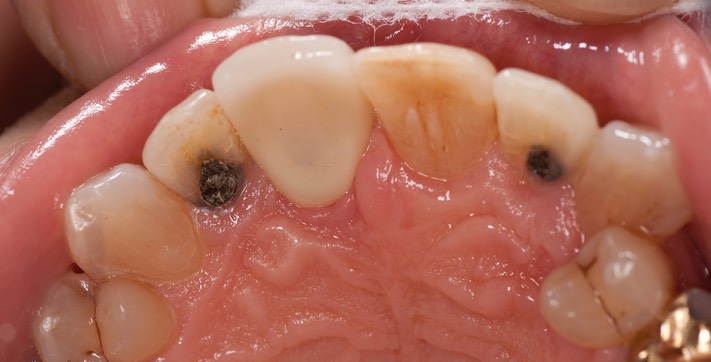

_DSC6643